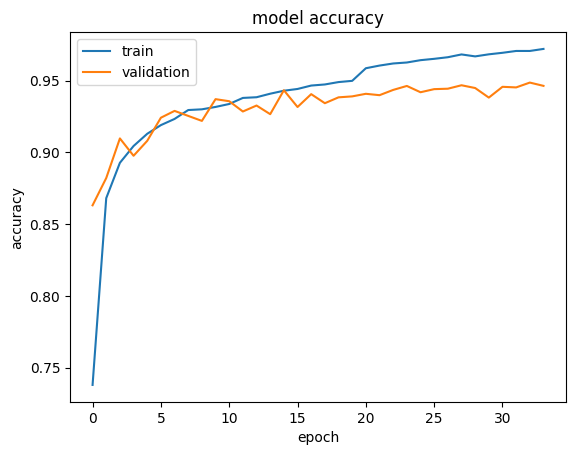

The dataset has been trained using our custom-made model dividing the whole data set into a batch size of 64 and later a portion of the dataset that has been extracted before the training as the test dataset and has been used in order to measure the performance of the model using various performance metrics. In addition to our custom model, the performance of the pre-trained model VGG-19 on the same dataset has been determined to get a clear comparative idea between the custom model and the pre-trained model. Accuracy of the overall dataset and precision, F-1 Score and sensitivity of each of the classes for each of the models has been calculated as the measurement of performance evaluation and has been depicted in Table V.

Firstly, if we focus on the models, the self-developed custom model has a clear superiority in terms of performance in all the performance metric. VGG-19 achieves an accuracy of 92.77% on the overall dataset, whereas the custom model reaches 94.87% exceeding that of VGG-19. Not only accuracy but also in terms of other metrics, the custom model always gains a higher value than the VGG-19 model in any of the classes. The precision, F-1 Score, sensitivity values of 0.921, 0.928 and 0.921 respectively of the CNV class from the custom model compared to the 0.898, 0.917 and 0.898 values from VGG-19 model can be given as an example that infers the previous statement. Fig 5 illustrates the confusion matrix of all the labels which is produced from the result of the proposed model

Secondly, another important observation from Table V is among the four classes CNV and Normal class has been comparatively superior in case of all the metrics, as the precision, F1-score and recall of CNV from the custom model are 0.967, 0.966 and 0.967 respectively and that values for the Normal cases are 0.977, 0.964 and 0.977 and similar scenario for the pre-trained model. The reason behind their better performance is the presence of their larger number of data and as the larger, the number of the data, the better the performance of any CNN model would be. The latter statement is also proven by the fact that the Drusen class has provided the poorest result and the quantity of data for this class is also the smallest So, in the end, it can be inferred that the performance of the self-developed custom model, as well as the pre-trained model, can easily be upgraded by collecting more data.

Overall, in terms of computation 6-layer custom model is more efficient than VGG-19. The parameters to be trained in our model is 423,460 wherein VGG-19 it is 21,011,740. Again, the model weight size of 6-layer custom model is less than 2 MB having a clear edge over the VGG-19.